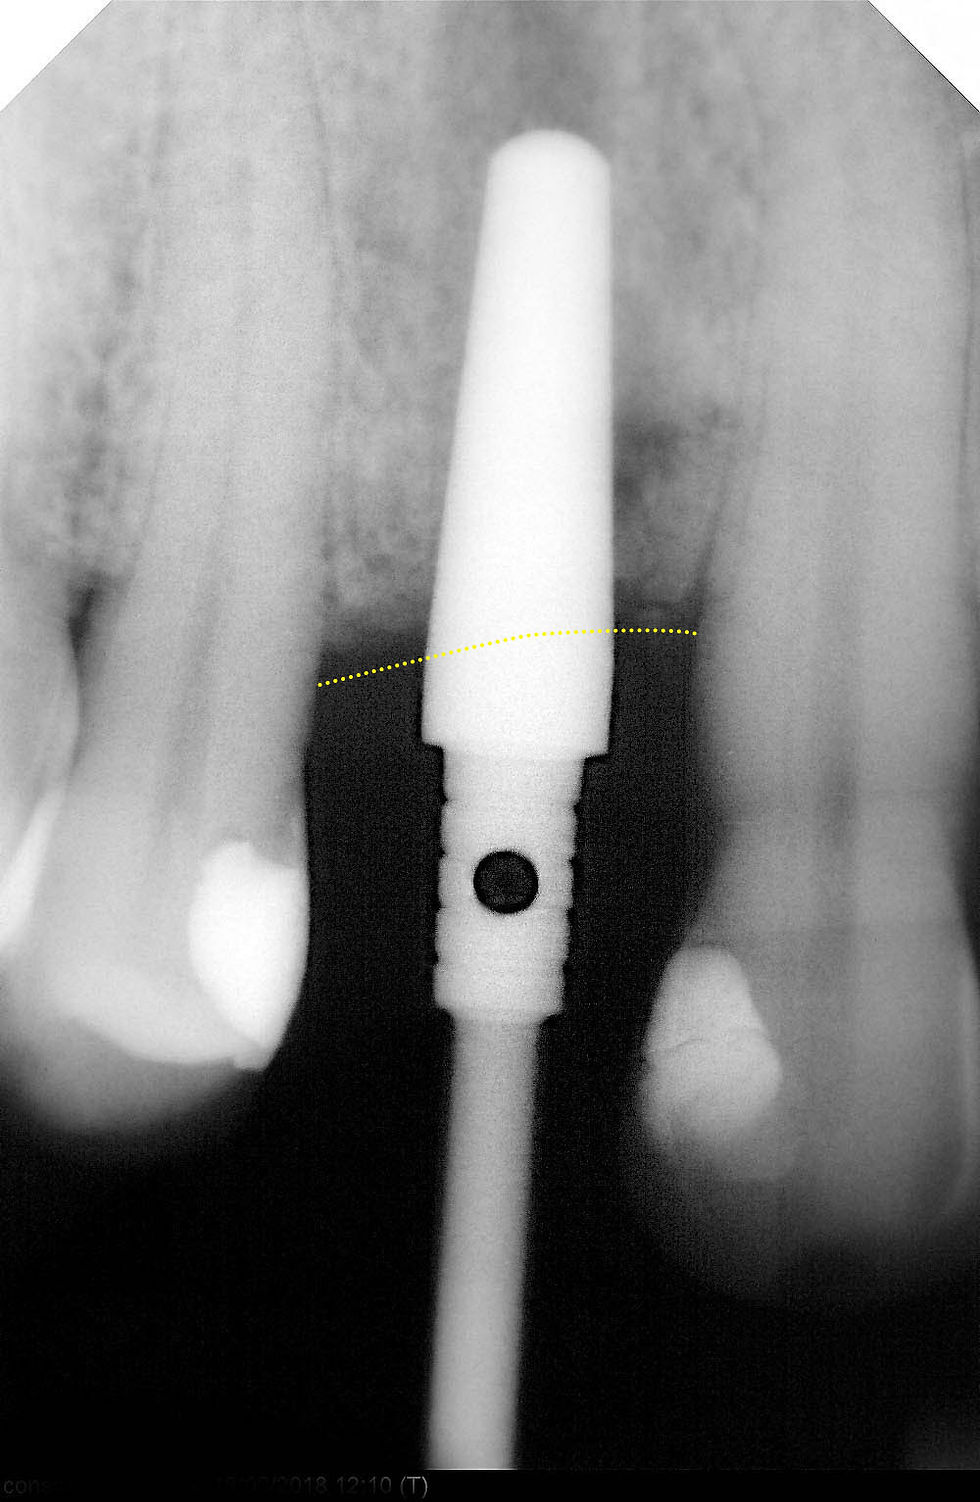

Radiographic control during implant insertion, to manage the irregular progression of the bone crest with the 2.8 mm neck of Prama RF.